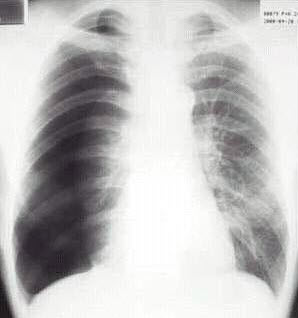

5、单项选择题

男,24岁,低热2周,咳少量痰。胸片示右上肺不均密度增高影,其中有空洞形成,血沉45mm/h。

最可能的诊断是()

A.右上肺炎

B.右上肺结核

C.右上肺癌

D.右上肺囊肿

E.右上肺脓肿